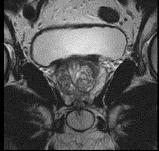

问题 男性,66岁,排尿困难多年,现感会阴部疼痛3个多月,指肛检查触及前列腺表面不规则,行MRI检查,如图所示,你认为最可能的诊断是 ( )

选项 A、前列腺钙化 B、前列腺出血 C、正常前列腺 D、前列腺癌 E、前列腺增生

答案 D